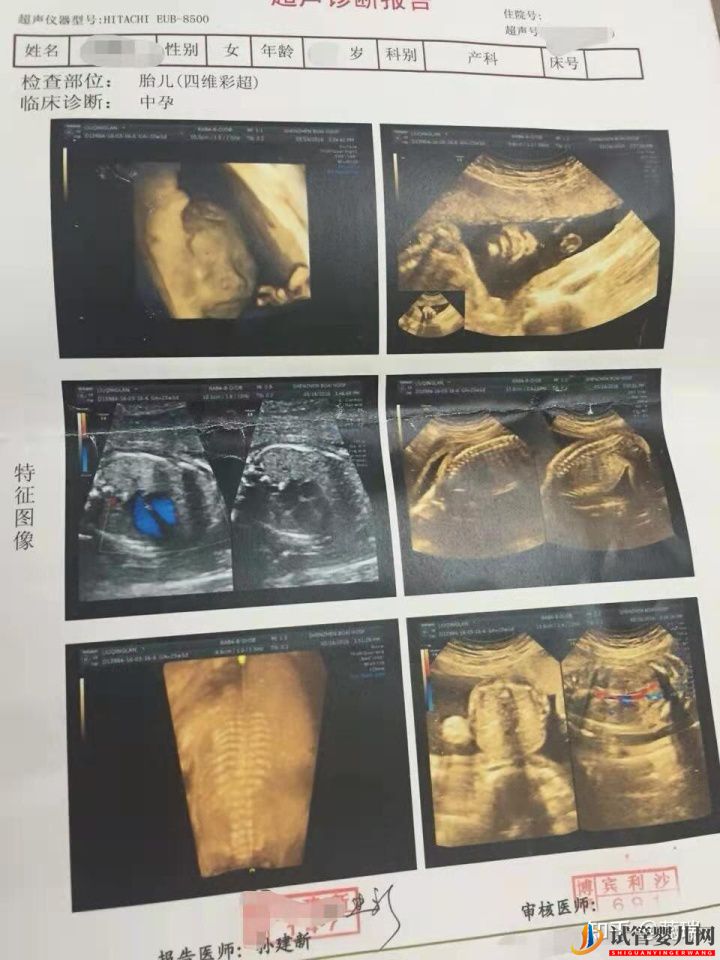

我是7月9號移植的,現(xiàn)在已經(jīng)快21周了,雖然過程辛苦了一點,但最后一切都是值得的。